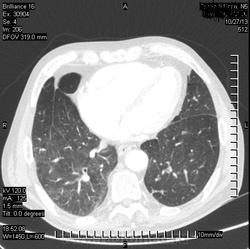

Коллега, а что, инфаркт искали? Или у Вас так окклюзии ЛА ищут? Интересно, а просто ОГК , для искл. пневмонии

( или инфаркт-пневмонии) слева?

Виноват. Не все вчера успел выложить.ТЭЛА.

Всё понятно стало. А, вот мне, как-то не очень легочная вена слева... Там все нормально? Или тоже тромб?

ТЭЛА слева, я правильно вижу?

Да. Слева.

Я не маститый "КТ-шник". На дежурствах в 2-3 часа ночи главное ухватить суть (на мой взгляд). Может быть тромб.